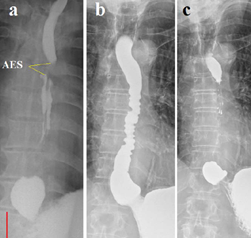

Figure 1 (Case 1) (а). High pressure in the stomach led to a reflex contraction of the UES and LES with tight filling of the esophagus. Assuming that the height of L-11 is approximately 2 cm, the length of the LES is 0.8 cm, which is significantly shorter than the minimum limit of normal (3.2 cm). This shortening indicates that the distal part of the LES has opened, and its walls are the walls of the stomach. The phrenic ampulla (red line) is sharply dilated (4.2 cm versus 1.5 cm in normal). The walls of the esophagus are uneven with asymmetric waviness. At level D-5, a symmetrical constriction 6 mm wide with smooth contours is determined (arrow). Between this narrowing and the lower point of the UES, a tight filling of the esophagus with smooth contours is determined. Barium lodged in the hypopharynx is visible at the very top of the x-ray indicates an inflammatory process. (b). After 5 minutes of rest, a spontaneous reflux of barium from the stomach into the esophagus is seen with a wide opening of the EGJ. The phrenic ampulla is smaller than in radiograph (a), but its distal contour is in the same place, on the lower contour of D-10 (upper red dot). The length of the open LES (between the two red dots) is 2.9 cm. Thus, the difference in length of the LES between (a) and (b) is due to the difference pressure in the stomach. At high pressure, the intra-abdominal portion of the LES opens. During reflux, the barium reached the level of D-5, where there was a narrowing in radiograph (a). Radiograph 1 b in the projection of the stomach shows a diagram of gradual shortening of the LES. From the norm to a sharp shortening of the LES, because of the opening of its distal part, which became the walls of the stomach.

Analysis. A sharp shortening of the LES, widening of the ampulla, asymmetrically uneven contours, and free reflux of barium from the stomach into the esophagus indicate GERD. Physiological narrowing at the D-5 level plays an important role in the clinical picture of the disease. It does not interfere with food intake, but during reflux, its contraction prevents acid from entering the mouth. Therefore, the patient never feels acid in the mouth. During sleep, this narrowing does not allow saliva to enter the distal esophagus. When a large volume of saliva accumulates between this narrowing and the UES, the esophagus between the narrowing and the UES contracts, and throws saliva into the pharynx, because of which the patient chokes on saliva and wakes up. This narrowing has symmetrical and smooth contours, which excludes stenosis. Its anatomy and physiology correspond to the sphincter that arises at the site of an anatomical narrowing of the esophagus, resulting from the retention of an acid bolus. We called this sphincter the "aorto-esophageal sphincter (AES). Barium lodged in the hypopharynx is visible on both radiographs. It indicates an inflammatory process, which is the cause of voice changes and a debilitating cough.

Diagnosis   GERD, pharyngitis, contraction of the AES. To reduce the tone of the AES, the patient swallowed a dense tablet with a diameter of 1.9 cm in the X-ray room. Complex treatment of GERD prescribed and a consultation with an otolaryngologist recommended.

Results   Starting from the next night, the patient did not wake up. The otolaryngologist confirmed the inflammatory process in the hypopharynx and prescribed pathogenic treatment. The treatment results are noted in Table 1. After a month, the index reflux (IR) decreased from 23 to 7.